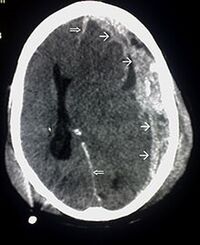

Die weißen Pfeile kennzeichnen die Blutergüsse im Gehirn

Die Gehirnerschütterung stellt eine Prellung des Gehirns dar. Schwere Kopfverletzungen sind beim Sport glücklicherweise eher selten. Jedoch sind Gehirnerschütterungen zB beim Fußball als Folge von Zusammenstößen mit Spielern beim Kopfball oder dem Torpfosten leider öfter zu sehen. Die Verletzten klagen über teilweise heftige Kopfschmerzen, Schwindelgefühle, manchmal auch über Übelkeit und Erbrechen, zudem können kurze Bewusstlosigkeit und Erinnerungslücken auftreten.